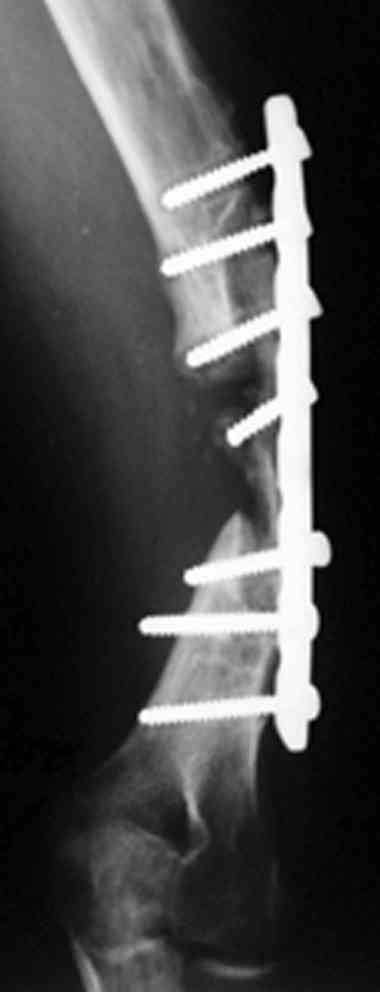

[Ortho] ложный сустав после остеосинтеза плеча

В подобном случае мы бы применили  чрескостный остеосинтез. Пример - в

приложении.